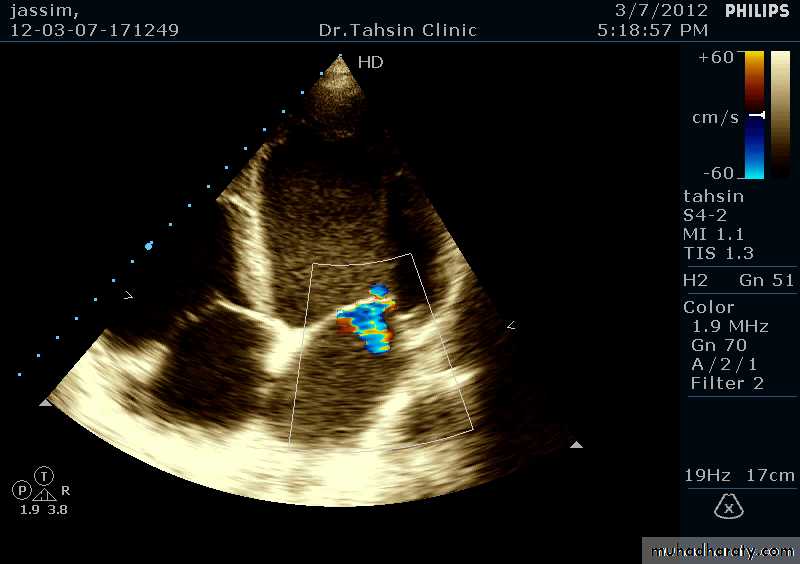

Two Dimensional Echocardiography

Ultrasound beam passing through the heart generates cross sectional images or “slices” of the heartVarious structures can be seen in real time

Two Dimensional Echocardiography indications

Assessment of LV functionDiagnosis & quantitation of severity of valvular lesions

Identification of vegetations

Identifying the source of systemic embolism

Detection of pericardial effusion

26

Doppler Echocardiography

Sound waves reflected from moving RBCs undergo frequency shiftThe faster the blood velocity , the greater the frequency shift

The direction of moving blood determines whether the reflected signal is positive or negative

The derived signal can be plotted graphically against timeOr, color can be assigned for the reflected signal and superimposed over the 2D image (color flow mapping)